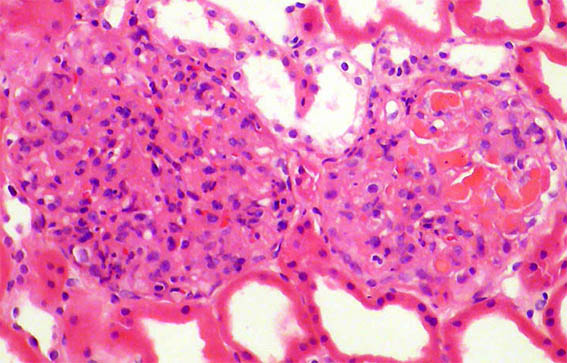

A 62-year-old woman is evaluated for erythema on both legs that has been developing for several weeks. There is no personal pathological history. On physical examination, they found systemic arterial hypertension, edema of the lower limbs, purpuric lesions on both legs, and Raynaud's phenomenon. In paraclinical tests, the hemoleukogram is normal; serum creatinine: 2.1 mg/dL, BUN: 39 mg/dL. ANA, anti-DNA, and ANCA: negative. C3: 82 mg/dL (84-180) and C4: 4.1 mg/dL (12-40). HIV and hepatotropic viruses: negative. In urinalysis there is microhematuria, leukocytes: 5/hpf, proteinuria: 4.2 g/24 hours, with mild hypoalbuminemia.

Figure 3.

H&E, X200.